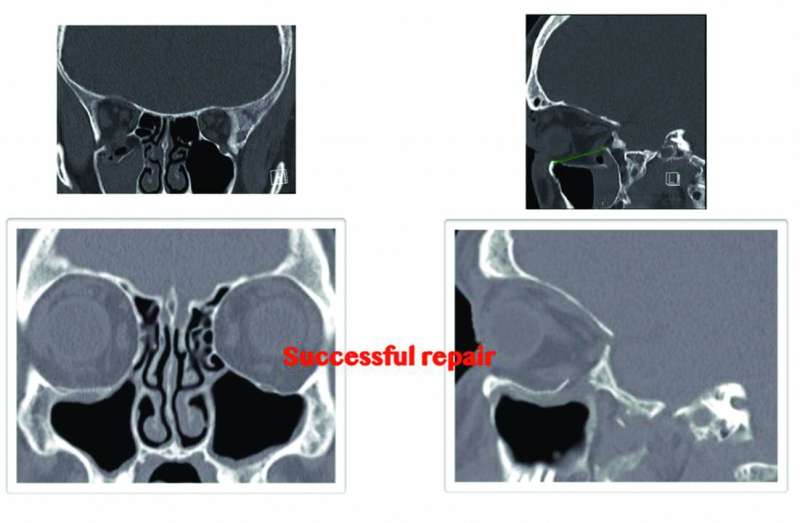

- ضرورة إجراء أشعة مقطعية عند الاشتباه في وجود كسر في قاع العين حتى في ظلّ عدم وجود آثار إكلينكية

ورأى أن بعض الجراحين يعتقد أن التدخل الجراحي يعتمد في المقام الأول على وجود العلامات السريرية، بيد أن الدارسات والأبحاث العلمية أثبتت أن نتائج فحوصات الأشعة المقطعية تكون مفيدة جداً حتى رغم عدم وجود آثار إكلينكية.

وأوضح أن إصلاح كسور قاع العين باستخدام جراحات مناظير الجيوب الأنفية هي تقنية جراحية تجميلية جديدة الهدف منها استعادة أفضل وظيفة فسيولوجية ممكنة مع إعطاء المريض مظهراً جمالياً دون الحاجة لإصلاح الكسر عن طريق فتح الجلد الخارجي وما ينتج عنه من تشوهات في شكل الوجه وهالة من آثار نفسية سيئة على المريض.

وأشار إلى أن استخدام المناظير يوفر للجراح رؤية بصرية واضحة مع سهولة في الوصول لقاع العين المكسور عن طريق الجيب الأنفي الفكي، مما يترتب عليه ترميم الكسور مع وضع شريحة لمنع هبوط الأنسجة الرخوية إلى الجيب الأنفي وتحرير العضلات العالقة داخل الشق الكسري.